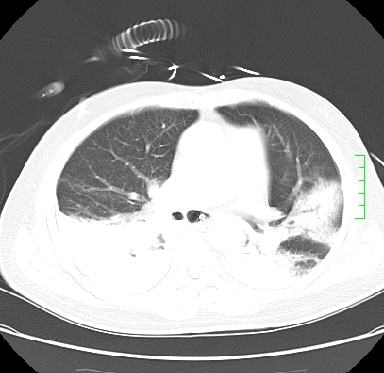

icu病人,几天都没明确诊断。m,76y,咳嗽、咳痰1周,伴气促,右胸痛入院,pe:t38.3c p135 r25 bp135/85。双肺可闻及大量湿罗音,心、腹未见明显异常。诊断:1心衰?2肺部感染?3冠心病?

11号ct

1)两肺感染性病变(右肺下叶肺脓肿可能)。2)双侧胸腔积液,以右侧为甚。

混合型肺水肿合并感染,肺膨胀不全,胸膜肥厚粘连包裹,同时肺内有陈旧性病灶。注意复查

考虑双肺感染、右肺下叶肺脓肿伴双侧胸腔积液。

ards,肺感染性病变,右下叶实变,双侧胸腔积液,右侧为著,叶间胸膜积液,右上肺陈旧性tb纤维灶,左室大。

考虑双肺感染、右肺下叶肺脓肿伴双侧胸腔积液,肺水肿。

考虑:双肺感染、右肺下叶肺脓肿,双侧胸腔积液,肺水肿.请结合临床.